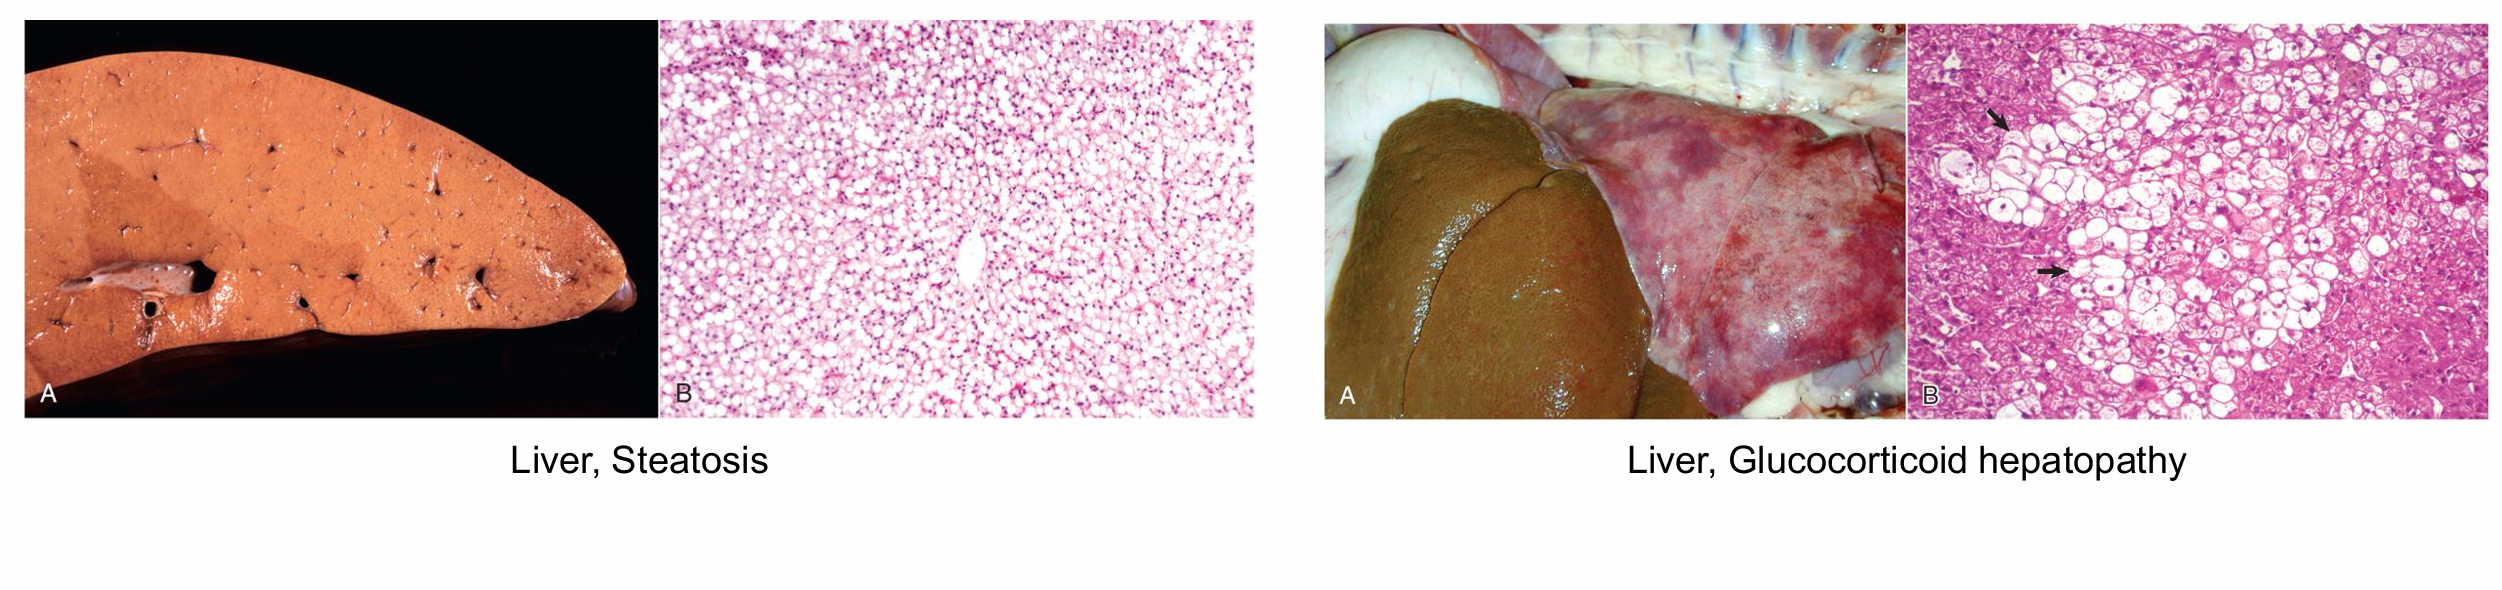

๋ํ์ ์ผ๋ก ์ง๋ฐฉ๊ฐ์ด ์๋ค. ๋๋ถ๋ถ์ ์ธํฌ์ ๊ณตํฌ๊ฐ ํ์ฑ๋์ด ์๋ค. ์ธํฌ๋ด์ ์ง๋ฐฉ ์ฑ๋ถ์ ์ฌ๋ผ์ด๋๋ฅผ ๋ง๋๋ ๊ณผ์ ์ค์ ์ป๊ฒจ๋ด๋ ค๊ฐ๊ธฐ ๋๋ฌธ์, ๋น์ด ๋ณด์ธ๋ค.

(์ผ) ์ ํ์ ์ธ ์ง๋ฐฉ๊ฐ - ๋๋ฆฌ๋ผ๋ฆฌํ๊ฒ ์ง๋ฐฉ์ด ์์, ๋๋ถ๋ถ์ ๊ฐ์ธํฌ์ ๊ณตํฌ ํ์ฑ / (์ค) ๊ณผ๋ํ gluticorticoid ์ฌ์ฉ์ผ๋ก ์ธํด glycogen (~lipid) ์นจ์ฐฉ

์ ํ์ ์ธ glycogen ์นจ์ฐฉ